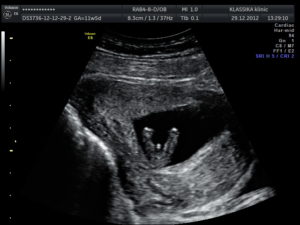

УЗИ 12 недель (первый скрининг, мальчик)УЗИ 12 недель (первый скрининг, мальчик)

УЗИ не может определить пол ребенка на таком раннем сроке. К 11 неделе у эмбрионов есть только половой бугорок, одинаковый у мальчиков и девочек.

Плодное яйцо определяется внутри матки как округлое образование с темной серединой и светлым ободком. Показатели, определяемые во время первого скрининга:

• КТР, или копчиково-теменной размер — позволяет определить срок, динамику развития эмбриона, в 11 недель составляет 33-35 мм;

• толщина воротникового пространства — по ней судят о наличии генетических аномалий, показатель не должен превышать 1,5 мм;

• размер головы составляет 1,9 мм;

• количество околоплодных вод — 20 мл;

• плацента до конца не сформирована;

• тонус матки не повышен;

• длина шейки матки не менее 3 см, внутренний и наружный зев закрыты.

Важный показатель нормально развивающейся беременности — отчетливое сердцебиение эмбриона. Сердце должно сокращаться с частотой 150 ударов в минуту.

На УЗИ в 11 недель можно увидеть формирующиеся части тела плода — голову, конечности. Между пальцами на руках и ногах уже нет перепонок. Можно разглядеть черты лица. Прослеживается позвоночник, печень и сердце.